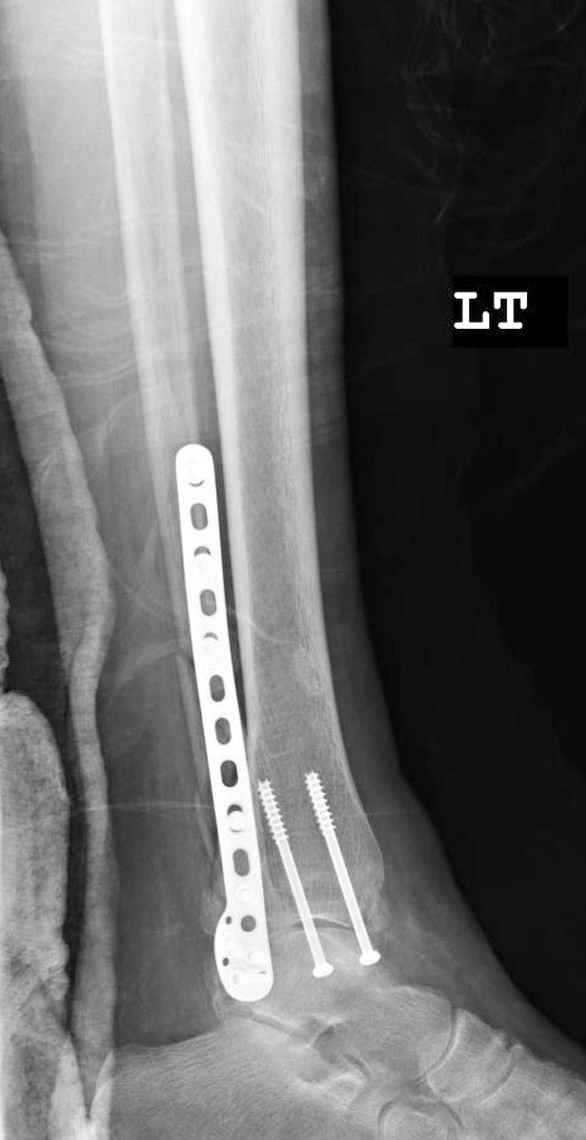

Ув. коллеги.

После проведенной дискуссии пришел к выводу, что трансартикулярная диафиксация не совсем приемлима с учетом современных методик остеосинтеза. Кроме того, вычитал, что хрящ разрушается на расстоянии до 0,5 см от места проведения спицы.

Пока я был в интернатуре, предпочитали осуществлять стабильный остеосинтез с ранней функцией. См. приложения и полнотекстный вариант

статьи.